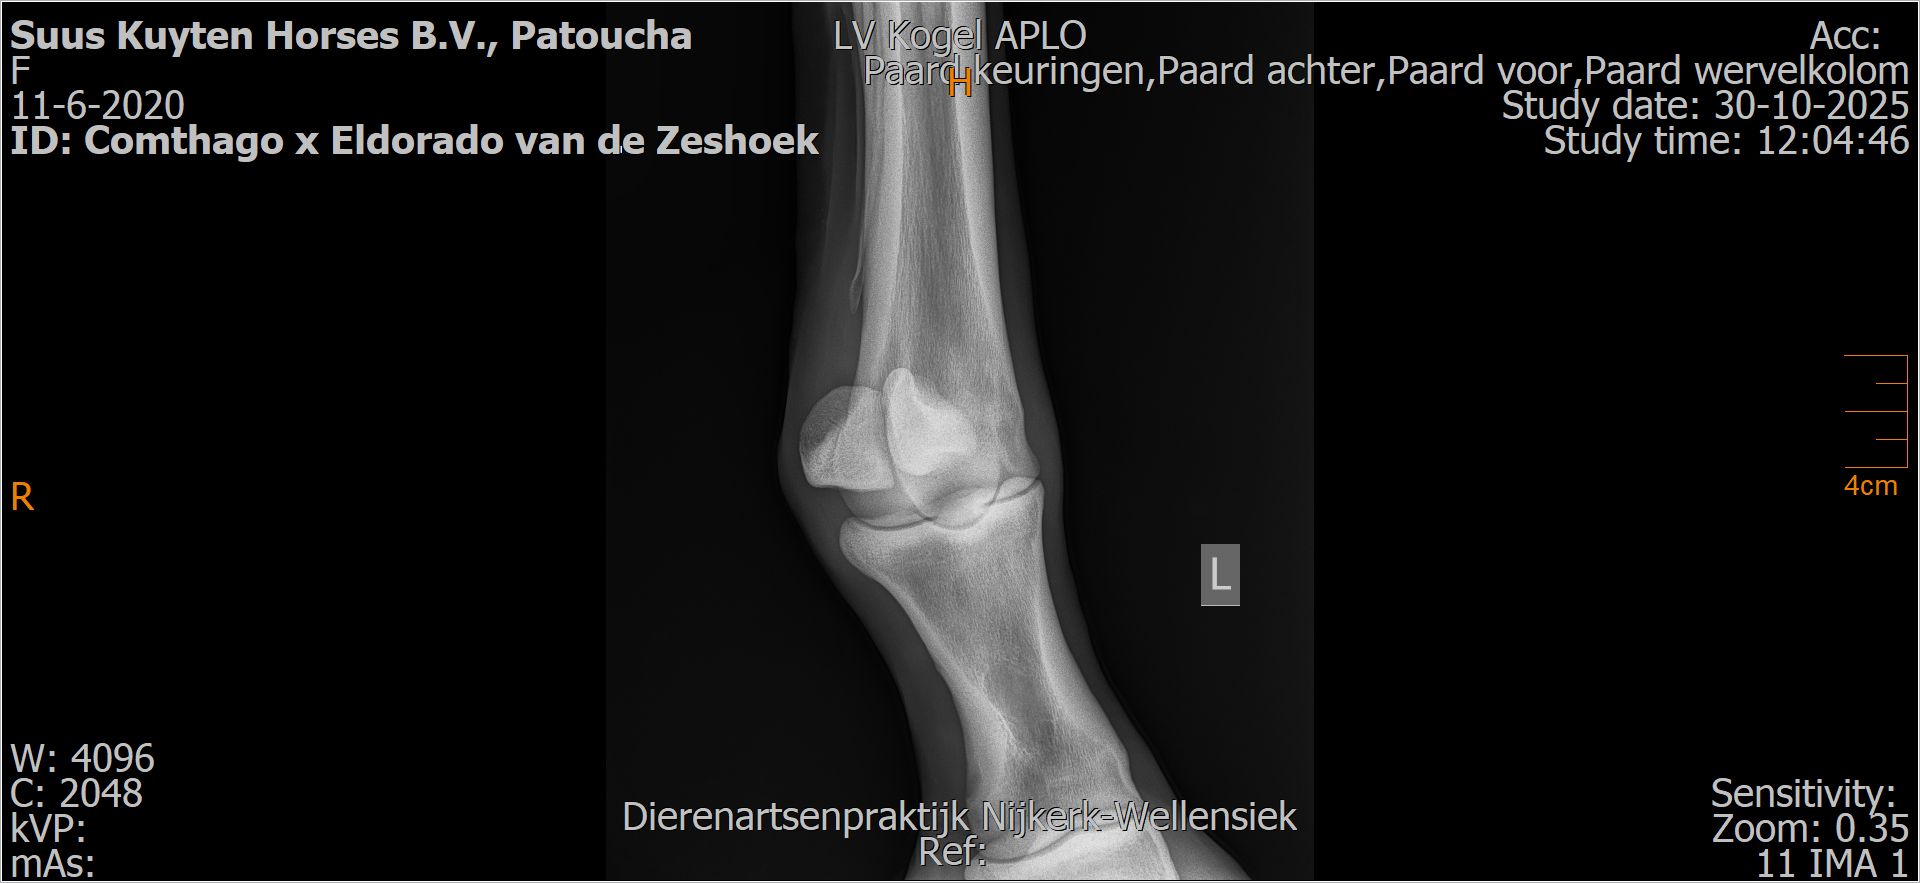

Patoucha

Leeftijd:

7

Röntgenfoto’s